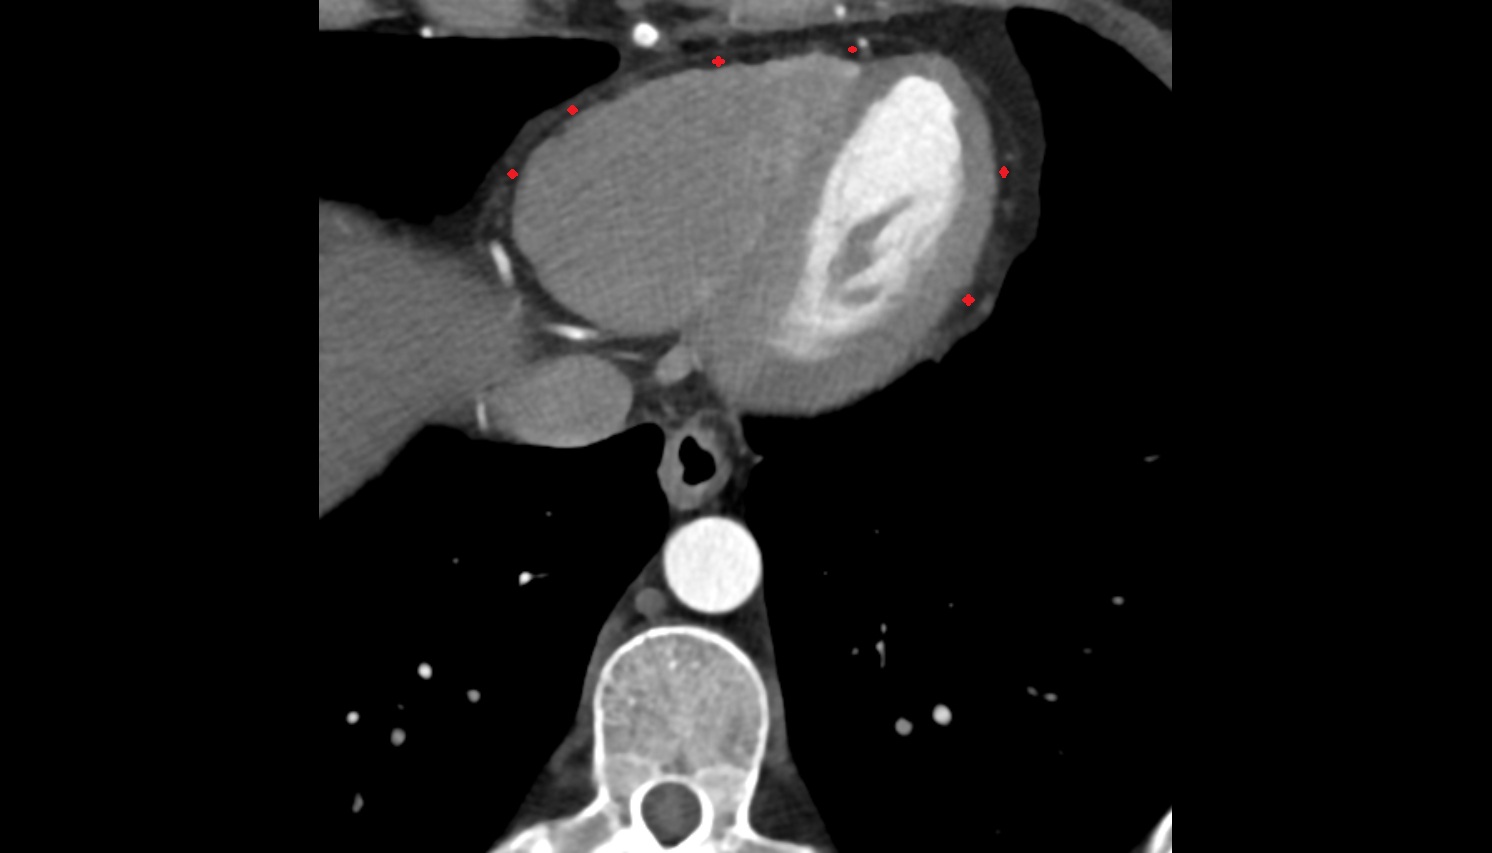

- Left anterior descending artery (LAD)

- Circumflex artery (LCx)

- Left main coronary artery (LMCA)

- Right coronary artery (RCA)

- First diagonal branch (D1) of LAD

- Second diagonal branch (D2) of LAD

- Right posterior descending coronary artery (Right PDA)

- Distal left anterior descending artery (dLAD)